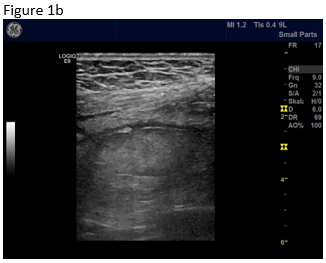

Figure 1: B-mode ultrasound using low frequency (a) and high frequency (b) revealed an isoechoic mass with a hypoechoic circumference. The mass was not adher-ent to the colon. Contrast enhanced ultrasound using low frequency (c) and high frequency (d) revealed that it was a non-enhancing segment of the omentum. Strain elastography showed that the lesion was stiffer than its sur-rounding tissue.